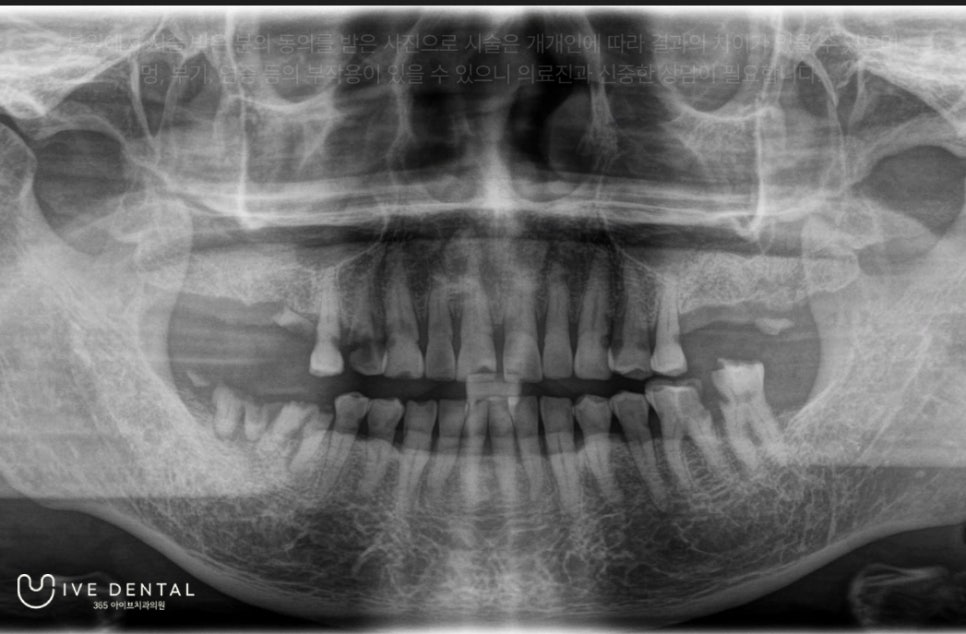

내원 시 찍은 X-ray 사진입니다.

잇몸 전체적으로 염증과 고름이 심하고 부식된 치아도 보입니다.

전체적으로 검진 후 살릴 수 있는 치아는 최대한 살리고 흔들림이 심하여 살릴 수 없는 치아는 뽑고 임플란트 시술을 하기로 하셨습니다.